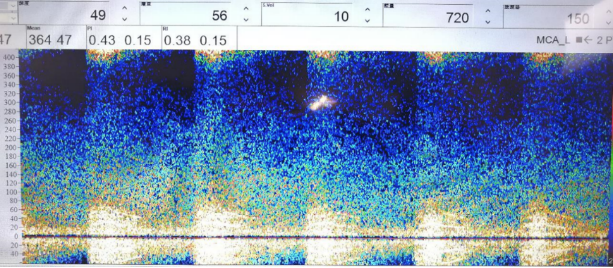

治疗前TCD

治疗后TCD狭窄频谱明显改善